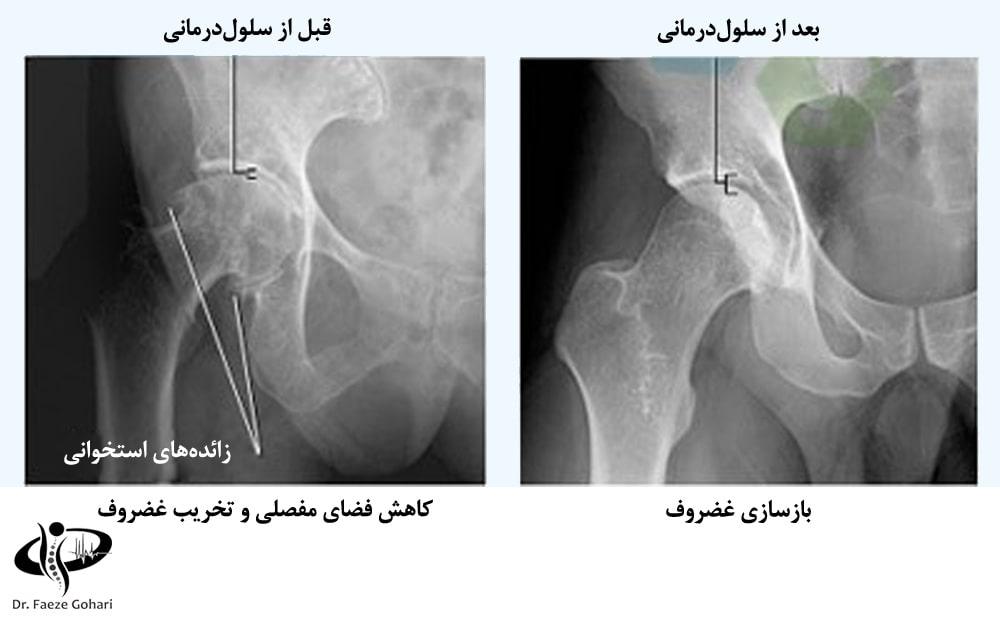

در این روش، سلولهای بنیادی به ناحیه آسیبدیده تزریق میشوند و با تولید غضروف جدید، به بازسازی طبیعی مفصل منجر میشوند. تجربه بالینی نشان داده است که حدود ۷۰% بیماران پس از ۲ روز از زمان تزریق، کاهش چشمگیر درد و بهبود قابلتوجهی را تجربه میکنند و روند بازسازی غضروف تا ماهها ادامه دارد. این درمان تا قبل از 70 سالگی بیشترین تاثیر را دارد و بسته به شدت آرتروز، ممکن است ۲ تا ۳ جلسه تزریق برای دستیابی به بهترین نتیجه لازم باشد.

تزریق سلولهای بنیادی و پیآرپی در آرتروزهای خفیف تا متوسط میتواند به بازسازی و ترمیم غضروف آسیبدیده کمک کند. در صورت تشکیل زائدههای استخوانی (استئوفیتها)، سلولدرمانی میتواند روند پیشرفت آنها را کند کرده، التهاب و درد را کاهش دهد و عملکرد مفصل را بهبود بخشد، اما قادر به حذف کامل زائدههای ایجادشده نیست. در مراحل پیشرفته آرتروز که غضروف به طور کامل تخریب شده است، این روشها بهعنوان یک درمان کمکی پس از جراحی برای بهبود بافتهای اطراف مفصل و تسریع روند بازتوانی استفاده میشوند. در ادامه، مواردی که سلولدرمانی در آنها انجام میشود، ذکر شده است.

در آرتروز، وقتی فضای بین مفصل به دلیل تخریب غضروف کاهش پیدا کرده و استخوانها به هم ساییده میشوند، سلولدرمانی میتواند با بازسازی غضروف، حرکت مفصل را راحتتر کرده و درد و التهاب را کاهش دهد. این درمان معمولاً در هفته اول بهبودی قابلتوجهی به همراه دارد و باعث نتایج زیر میشود.